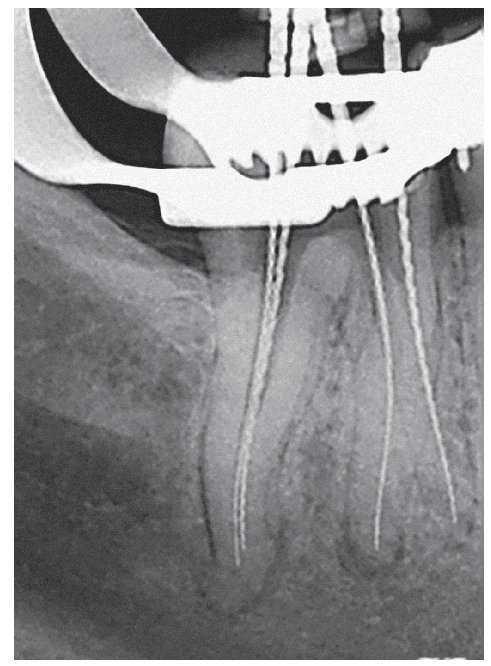

Figura 1a. Radiografía diagnóstica ortorradial del diente 43: una imagen radioopaca «interrumpe» el conducto radicular en el tercio medio de la raíz, fuerte curvatura apical del conducto radicular hacia mesial.

Figura 1b. En el segmento coronal de la raíz se observan dos conductos radiculares orientados en sentido vestibulolingual que están unidos por un istmo.

Figura 1c. En la proyección excéntrica de la conductometría se aprecia claramente la configuración tipo VI de Vertucci: los dos conductos radiculares están separados por un septo en el tercio medio y se unen nuevamente por debajo de éste mediante un istmo en el que se encuentran todavía restos de CaOH de la primera sesión. Los dos conductos muestran una trayectoria divergente en sentido apical para acabar en un foramen apical cada uno.